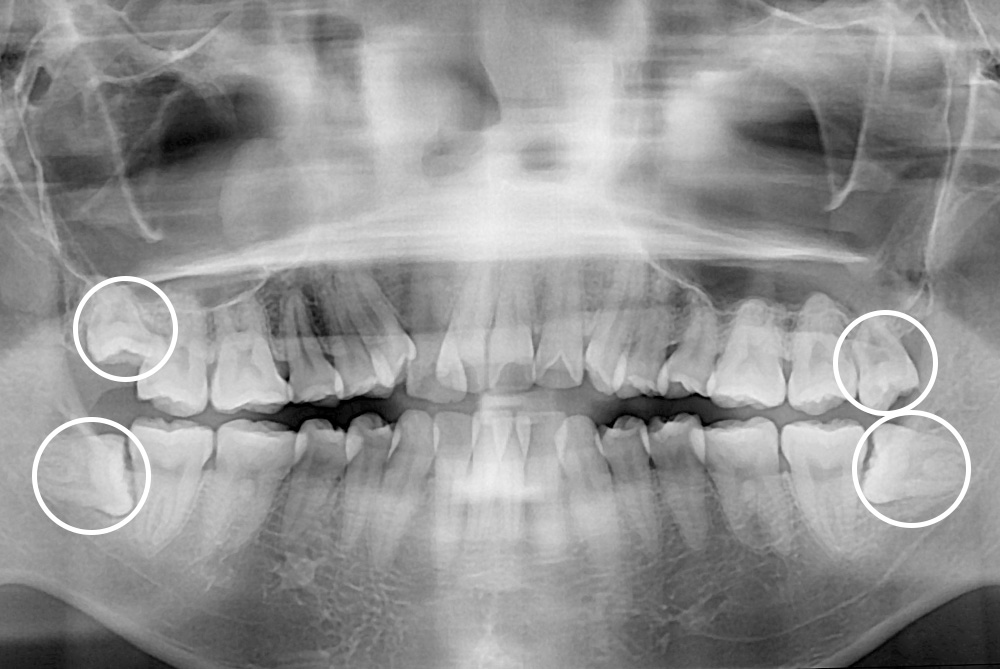

[사랑니] 매복 사랑니 발치

치료후 : 2018-07-20

세종치과는 구강악안면외과학 박사이신 원장님이 발치하는 치과입니다.